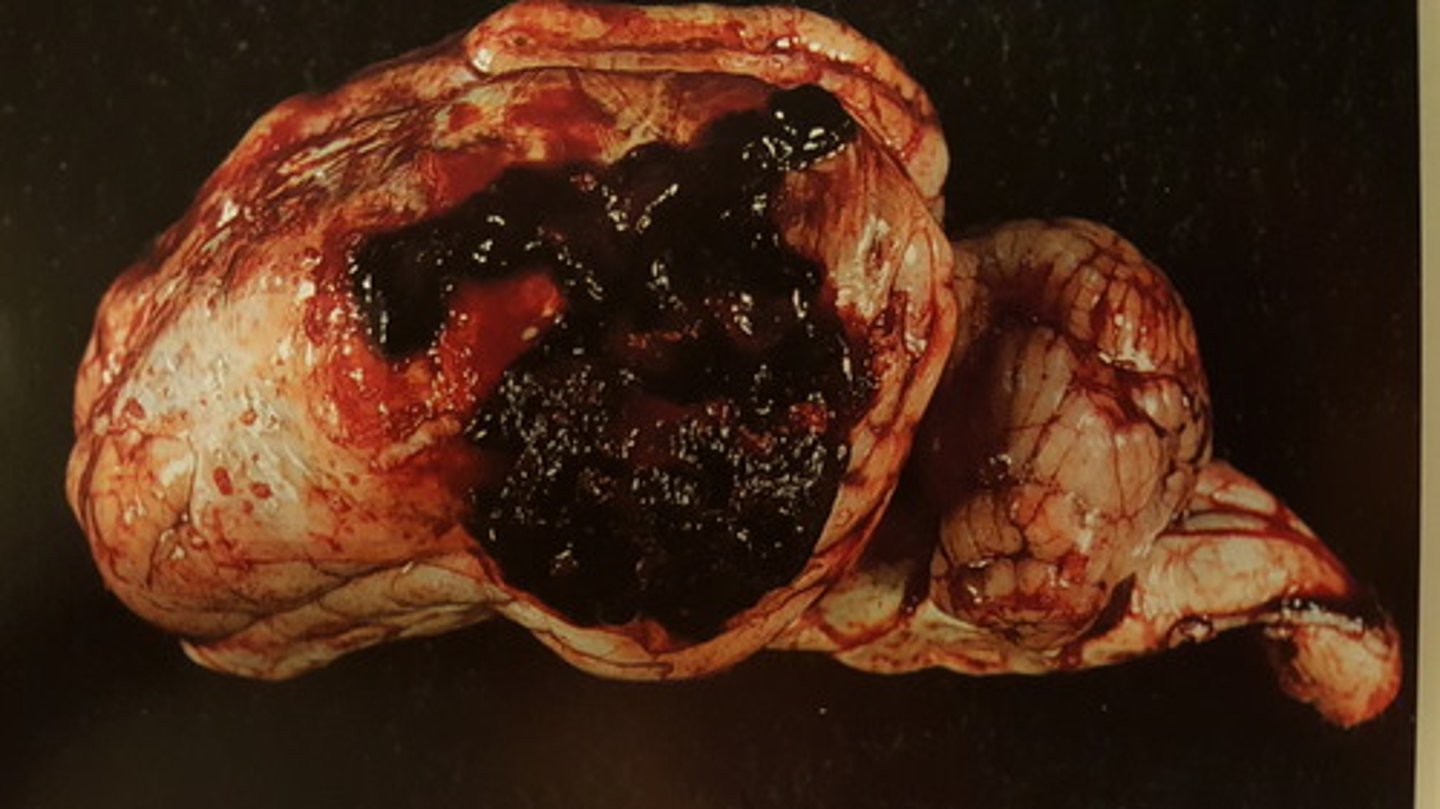

Akut, hæmorrhagisk og nekrotiserende hepatitis.

Ætiologi: infektion med Fasciola heptatica

Lever fra får, hvad er den patoanatomiske diagnose og ætiologien?